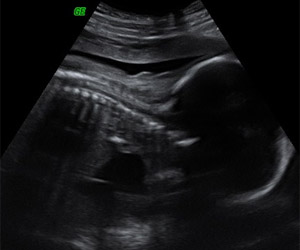

Ecografía de la semana 18: cabeza y cervicales. Podemos ver un feto boca abajo. Se visualiza claramente la cabeza (a la derecha) y la columna, con las vértebras cervicales y dorsales.

Ecografía de la semana 18: columna. Corte de la columna fetal con las vértebras cervicales, dorsales, lumbares y sacras. Podemos ver la integridad de la columna, lo descarta el diagnóstico de escoliosis.